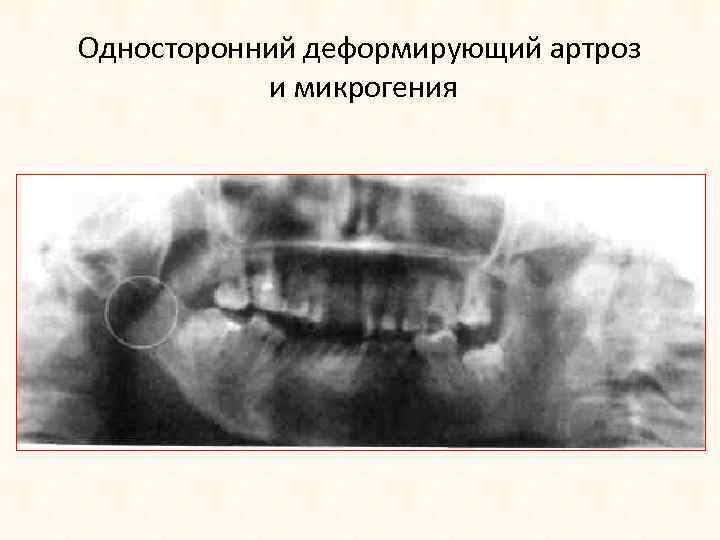

Односторонний деформирующий артроз и микрогения